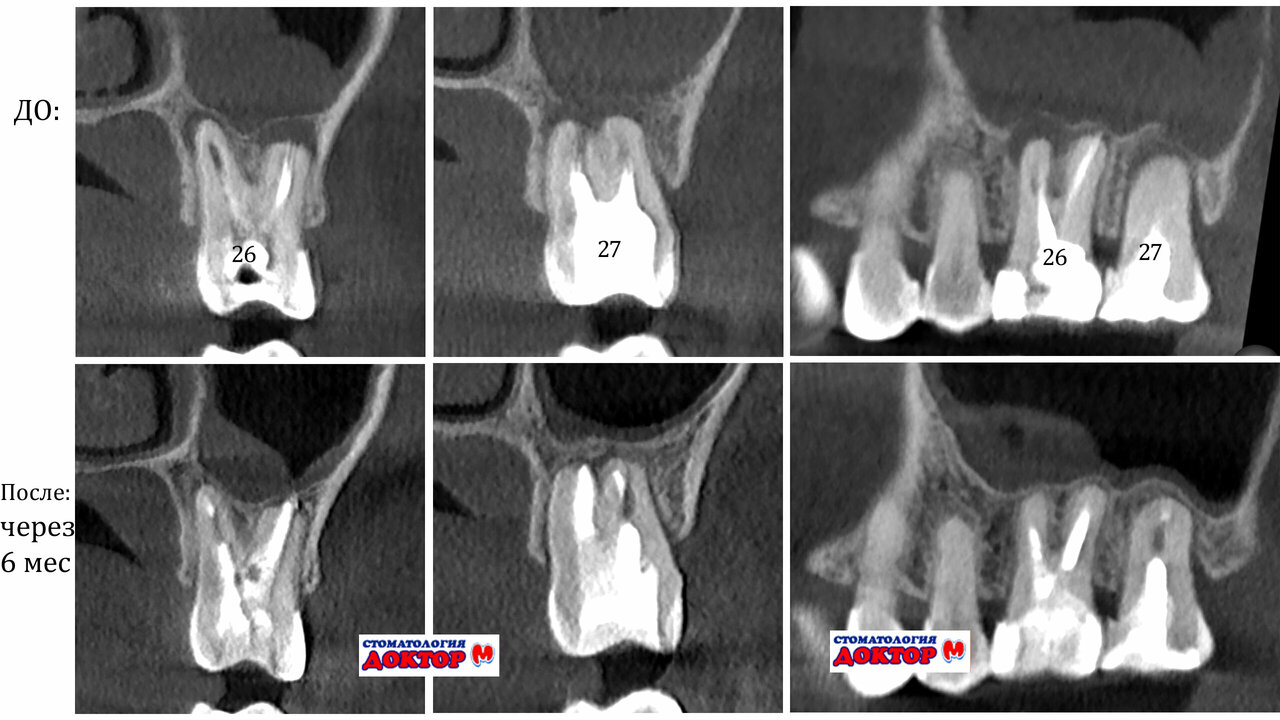

Перелечивала здесь два зуба, шестерки, очень сложные оказались, до этого два доктора сказали что не справятся. У Рустама получилось отлично, каналы вылечены, зубы спасены. А это самое главное. Спасибо, доктор!

Среди основных направлений работы: лечение кариеса, пломбирование, удаление зубов, протезирование, установка виниров и коронок, а также профессиональная гигиена. Отдельное внимание уделяется эстетической стоматологии, включая отбеливание и реставрацию зубов. В клинике проводятся сложные процедуры, такие как лечение периодонтита, кисты зуба и эндодонтическая терапия.

Стоматология оснащена современным оборудованием, включая рентгенографию, и предлагает услуги квалифицированных специалистов: стоматологов-терапевтов, хирургов, имплантологов, ортопедов и гнатологов. Клиника обеспечивает безболезненное и комфортное лечение с гарантией качества.